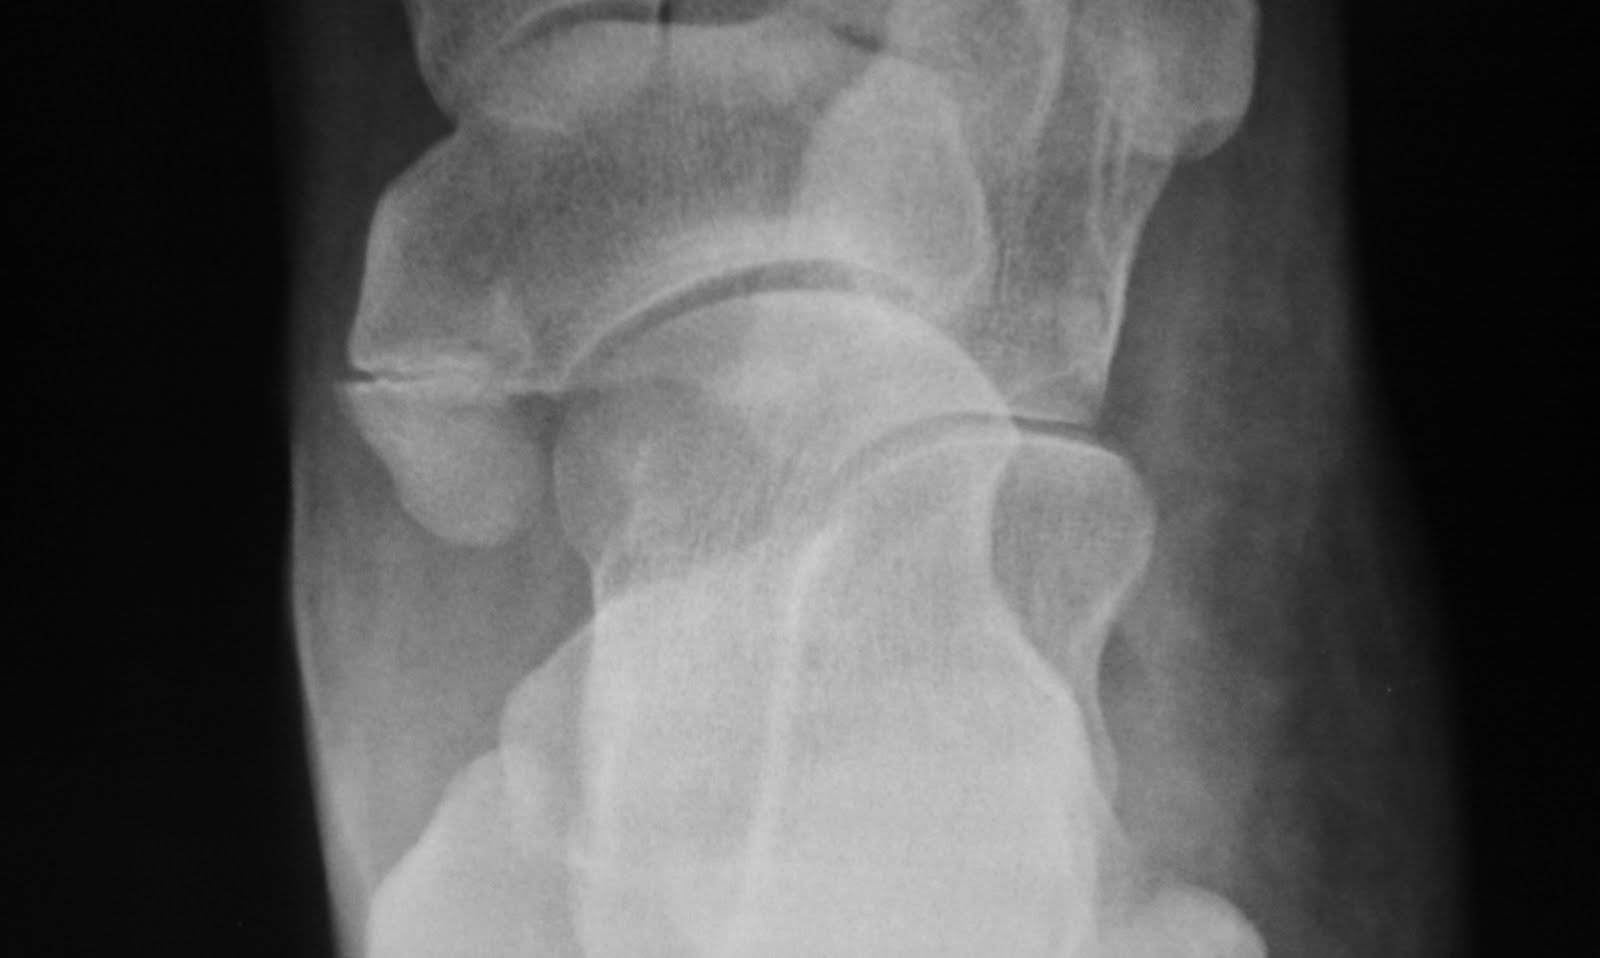

Accessory Navicular Bone Xray . there are three types of accessory navicular, with the most symptomatic being type 2 accessory navicular bones, because they are often connected to the. the mr imaging findings of painful type ii accessory navicular bone are a persistent edema pattern in the. The calcification process occurs at a variety of different times in life depending on. the accessory navicular syndrome, also known as os naviculare syndrome occurs when a type ii accessory. the accessory navicular (or tibiale externum) bone is located at the posteromedial aspect of the foot adjacent. symptomatic accessory navicular bones may appear as a 'hot spot' on bone scan and on mri bone marrow edema can be seen. acessory navicular is a common idiopathic condition of the foot that presents with an enlargement of the.

Accessory navicular bone on plain Xray in 5 cases; case 1 (type II Accessory Navicular Bone Xray the accessory navicular syndrome, also known as os naviculare syndrome occurs when a type ii accessory. symptomatic accessory navicular bones may appear as a 'hot spot' on bone scan and on mri bone marrow edema can be seen. acessory navicular is a common idiopathic condition of the foot that presents with an enlargement of the. The calcification. Accessory Navicular Bone Xray.

The foot radiographs of three different types of accessory navicular Accessory Navicular Bone Xray the mr imaging findings of painful type ii accessory navicular bone are a persistent edema pattern in the. the accessory navicular syndrome, also known as os naviculare syndrome occurs when a type ii accessory. there are three types of accessory navicular, with the most symptomatic being type 2 accessory navicular bones, because they are often connected to. Accessory Navicular Bone Xray.